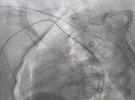

Пацієнткою стала 12-річна дівчинка, яка страждала на симптоматичну артеріальну гіпертензію, повідомляє Клінічна лікарня швидкої медичної допомоги Львова у Facebook. При обстеженні у дитини виявили вроджену ваду серця - коарктацію аорти. Це стан, при якому звужений просвіт аорти, від чого розвивається підвищений тиск у верхній половині тіла.

Сучасні технології на основі результатів обстеження допомогли провести віртуальну реконструкцію анатомії аорти та її гілок. Це допомогло обрати найбільш сучасну та малотравматичну тактику подальшого лікування. Вроджену ваду ліквідували за допомогою малоінвазивної ендоваскулярної процедури - встановлення стента в просвіт судини.